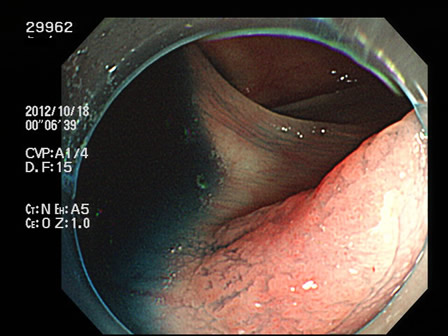

29901 29904 29905 29906 29907 29908 29909 29913 29915 29917 29918 29921 29925 29926 29927 29928 29930 29934 29936 29938 29939 29940 29941 29942 29943 29944 29945 29947 29948 29949 29955 29959 29961 29962 29965 29968 29972 29975 29979 29980 29981 29983 29985 29986 29987 29989 29993 29996 29998 29999・・・・・・・の50名

上記100名より抽出した平坦・陥凹型腺腫(=癌化の危険が高いが見落としやすい病変)の内視鏡写真